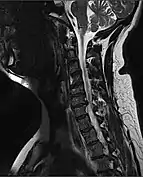

| MRI of a fractured and dislocated cervical vertebra (C4) in the neck that is compressing the spinal cord | |

A radiographic evaluation using an X-ray, CT scan, or MRI can determine if there is damage to the spinal column and where it is located.[9] X-rays are commonly available[88] and can detect instability or misalignment of the spinal column, but do not give very detailed images and can miss injuries to the spinal cord or displacement of ligaments or disks that do not have accompanying spinal column damage.[9] Thus when X-ray findings are normal but SCI is still suspected due to pain or SCI symptoms, CT or MRI scans are used.[88] CT gives greater detail than X-rays, but exposes the patient to more radiation,[90] and it still does not give images of the spinal cord or ligaments; MRI shows body structures in the greatest detail.[9] Thus it is the standard for anyone who has neurological deficits found in SCI or is thought to have an unstable spinal column injury.[91]